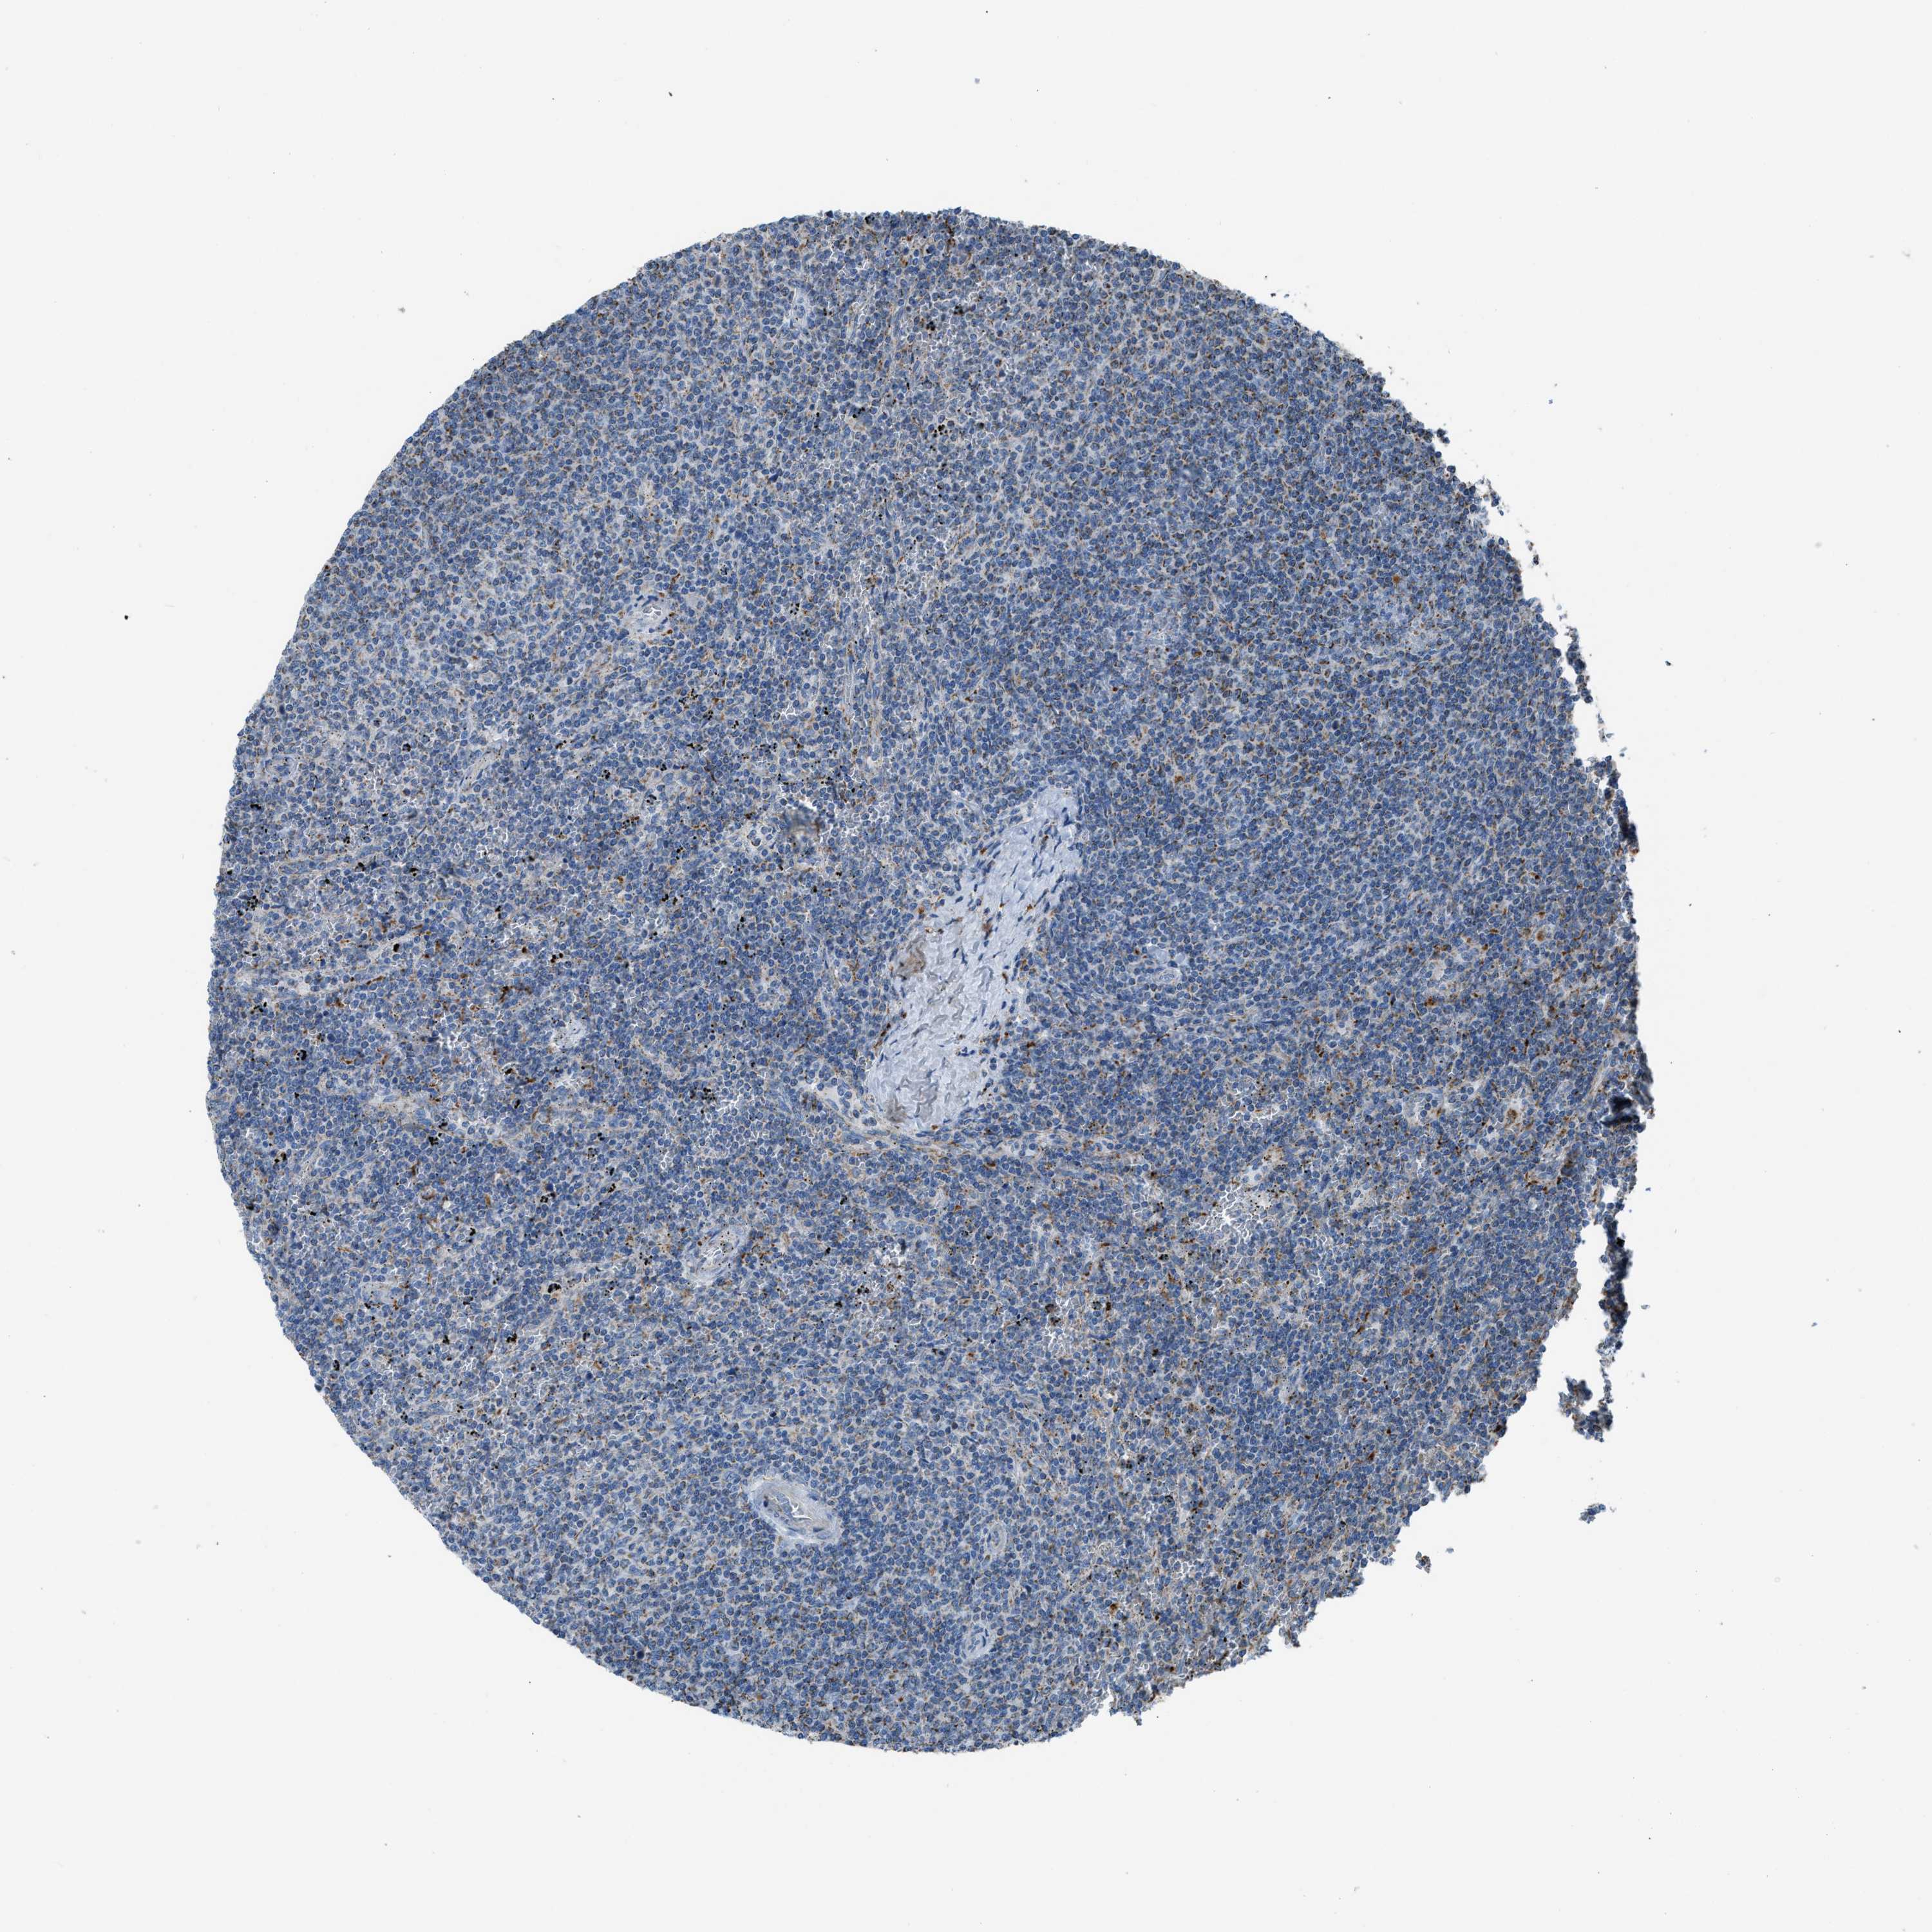

CANCER LYMPHOMA Show tissue menu

LYMPHOMA - Protein expressioni

A mouse-over function shows sample information and annotation data. Click on an image to view it in a full screen mode. Samples can be filtered based on level of antibody staining by selecting one or several of the following categories: high, medium, low and not detected. The assay and annotation is described here.

Antibody stainingi

Antibody staining in the annotated cell types in the current human tissue is reported as not detected, low, medium, or high, based on conventional immunohistochemistry profiling in selected tissues. This score is based on the combination of the staining intensity and fraction of stained cells.

Each image is clickable and will lead to virtual microscopy that enables deeper exploration of all samples and also displays staining intensity scores, fraction scores and subcellular localization as well as patient and tissue information for each sample.

Antibody HPA016552

Staining

High

Medium

Low

Not detected

Intensity

Strong

Moderate

Weak

Negative

Quantity

>75%

75%-25%

<25%

None

Location

Nuclear

Cytoplasmic/membranous

Cytoplasmic/membranous,nuclear

Hodgkin's disease, NOS

Malignant lymphoma, non-Hodgkin's type, High grade

Malignant lymphoma, non-Hodgkin's type, Low grade